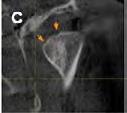

The pathway of a sinus tract that develops from a necrotic pulp is through the alveolar bone and emptying purulent exudate into the oral cavity. The stoma can be on the attached gingiva, alveolar mucosa or gingival sulcus. It can also empty on the buccal or lingual surface (Figures 1A, B). This is determined by the proximity of the apex to either the cortical plate and/or the density of the bone. Finally, it can also drain extraorally (cutaneous sinus tract) (Figures 2A, B).[3-5]

Figure 1B: Sinus tract was traced with size 35 gutta-percha. Periapical radiograph revealed origin of sinus tract was periapical lesion associated with distal root of first molar not second molar, indicating possibly wrong tooth had been treated. Figure 1A: Patient was referred to endodontist for evaluation because sinus opening had not healed after endodontic therapy on lower left second molar. Patient was asymptomatic and had been so prior to initiation of therapy; however treatment was initiated because of diagnosis of sinus tract opening facial to second molar

Figure 2B: By gently removing existing scab, sinus opening was evident. It was traced with size #25 gutta-percha cone to lower right central incisor that was unresponsive to cold and EPT. Figure 2A: Patient reported to clinic with history of persistent “pimple” on her chin. Plastic surgeon had excised pimple, but it reappeared within few weeks. fistula is lined with epithelium that may or may not be filled by granulomatous tissue.[22-26]